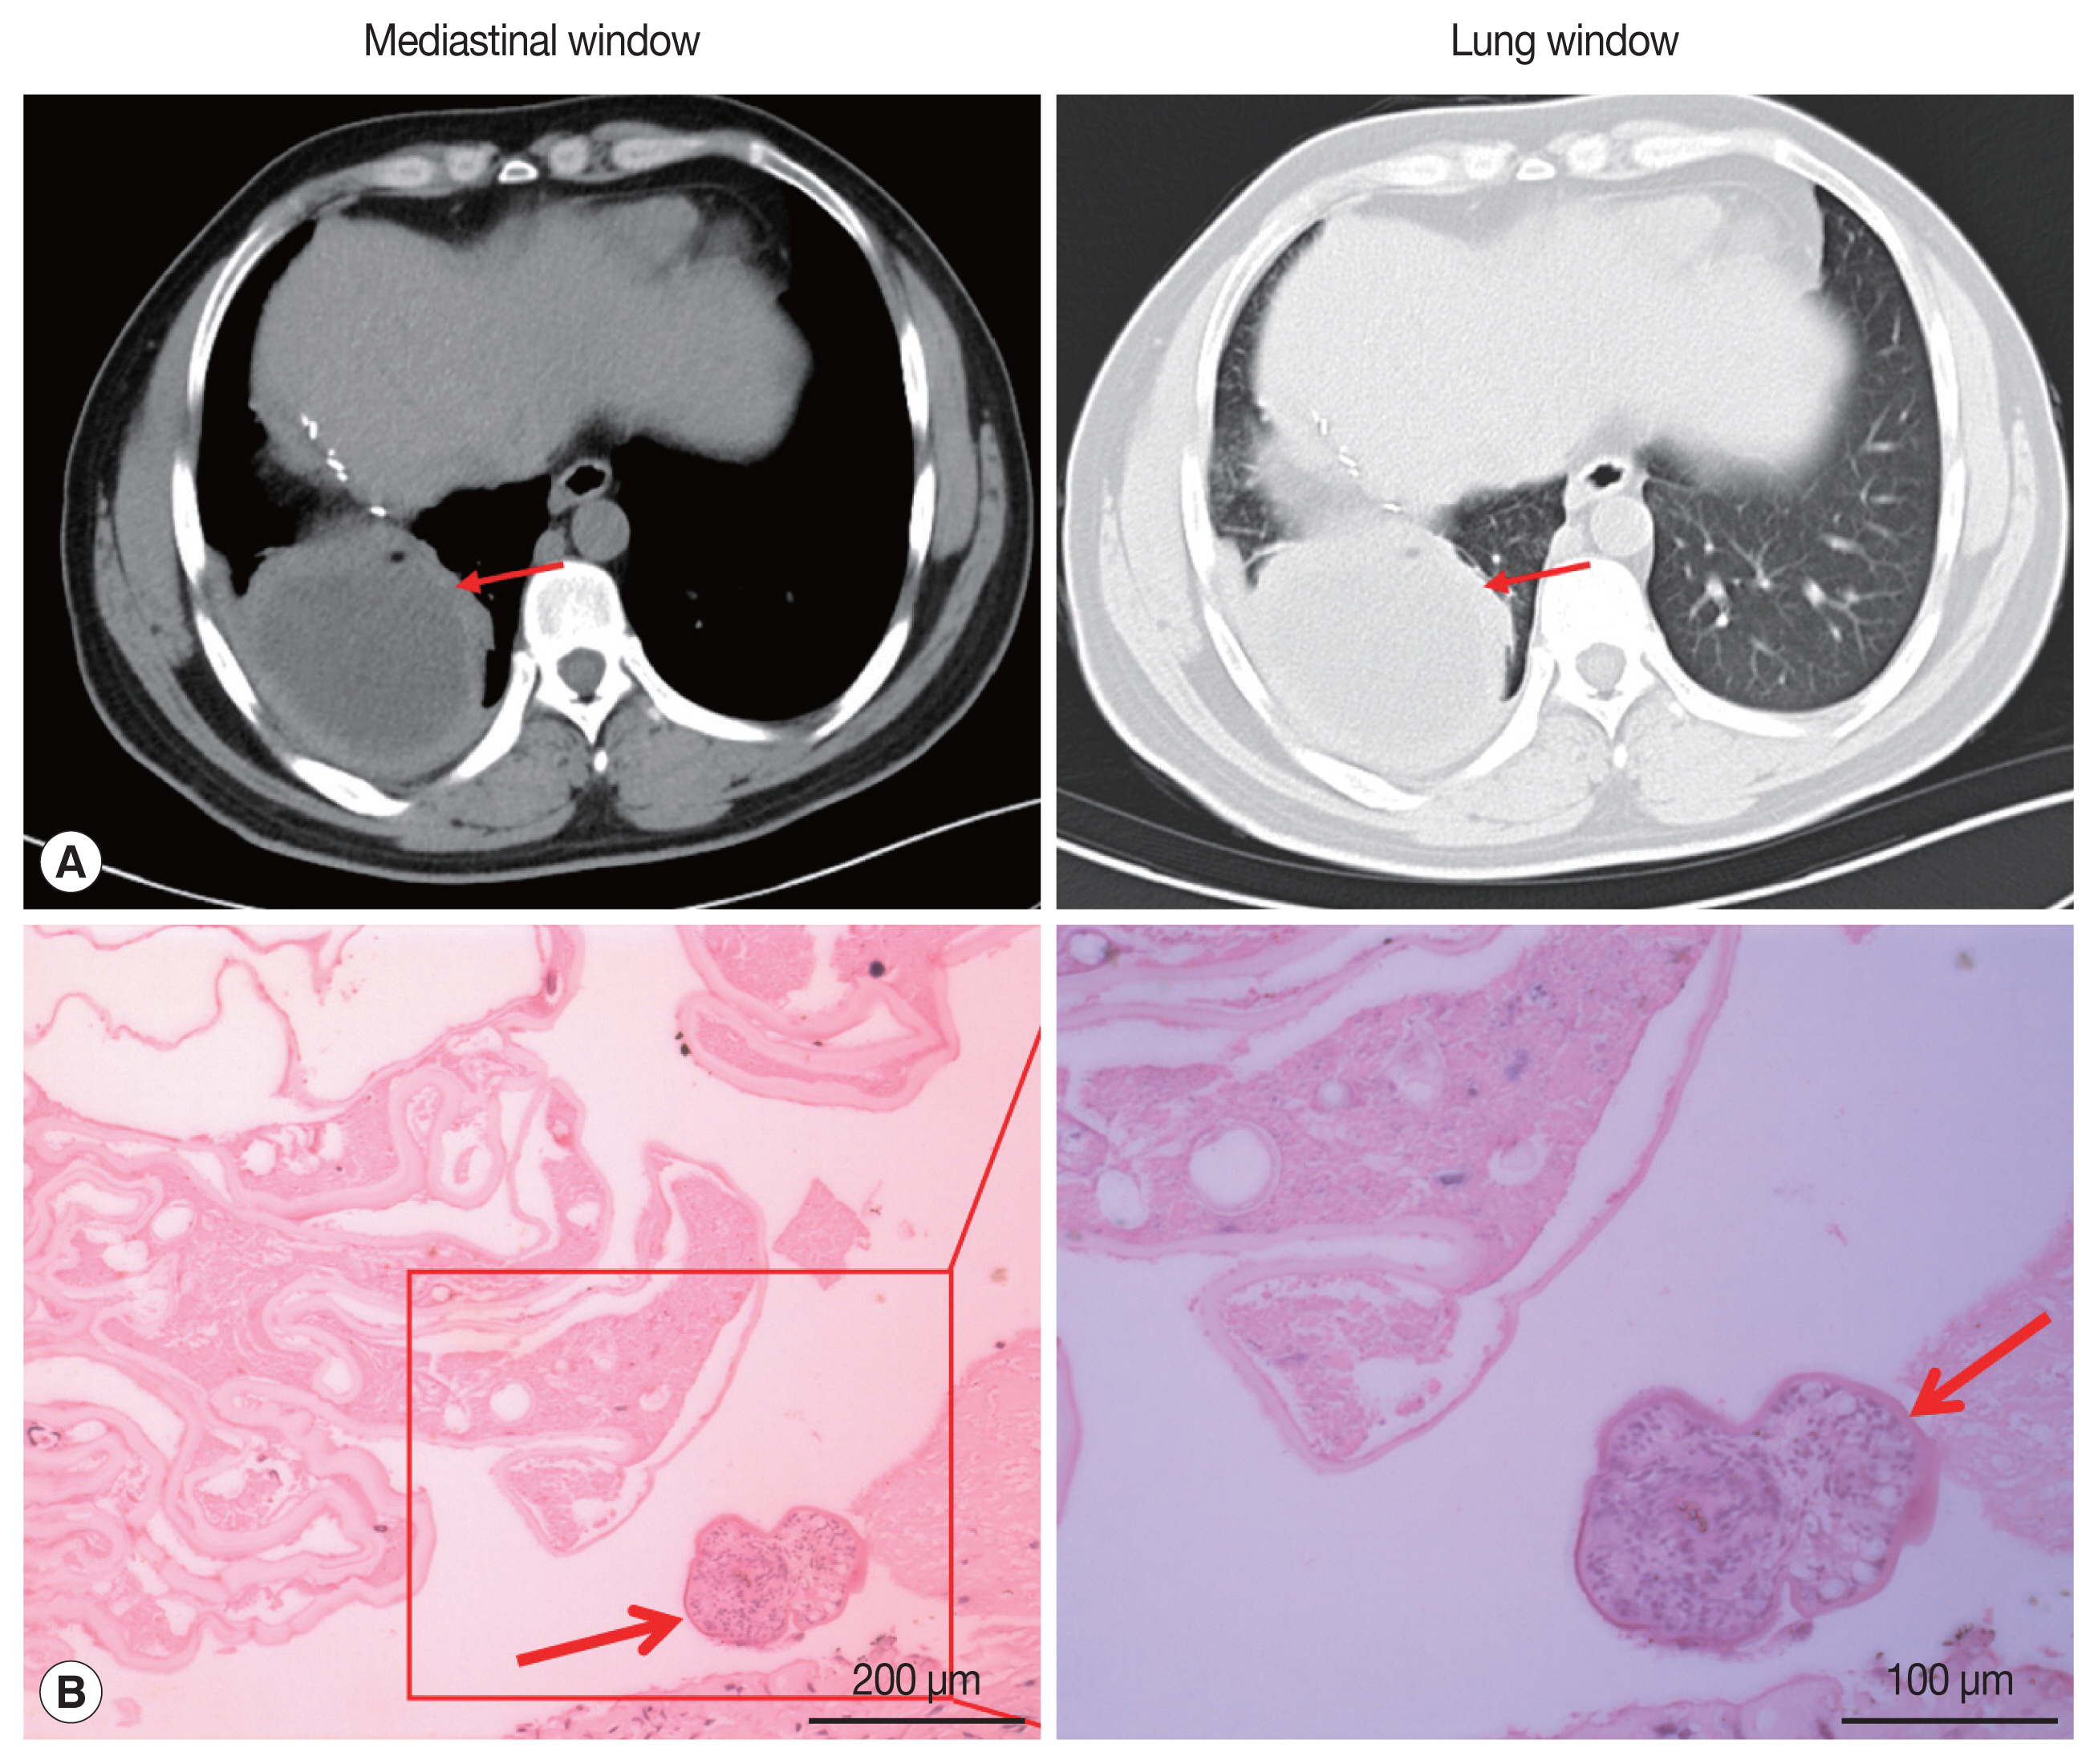

On January 3, 2017, a 34-year-old Tibetan Chinese man came to the Department of Neurosurgery at the Qinghai University Affiliated Hospital for treatment with severe upper abdominal pain. The patient lived in pastoral areas of Qinghai Province for a long time and had been in good health before. Physical examination touched a mass in the upper abdomen, which was 18.0×16.0 cm in size, accompanied by tenderness. Ultrasound Color Doppler of the upper abdomen presented a 11.6×11.2 cm mixed mass in the right posterior lobe of the liver (Fig. 1A). The dynamic 3-phase Computed Tomography (CT) examination of the liver demonstrated a round lesions (about 9.6×8.9 cm) in the liver S7-6 segment, with a thick wall, and a CT value of about 16 HU. Calcification could be observed in the lesion, and no enhancement was seen in the lesion after enhancement (Fig. 1B). Chest X–ray and laboratory findings were all within normal limit. Additionally, hydatid serological IgG ELISA remained negative. Stool examination showed no parasites or eggs. Based on these findings, the patient was diagnosed as hepatic AE. The patient underwent right hepatectomy and cholecystectomy on September 6, 2017. During the operation, there existed obvious adhesion between the lesion and the lateral abdominal wall, which invaded the diaphragm and lateral peritoneum. Postoperative pathological examination confirmed AE disease. The histopathological examination showed obvious laminated layer (Fig. 1C), intensely colored by the periodic acid-Schiff stain without a germinal layer (Fig. 1D). These morphological findings verified AE. The patient fully recovered after surgery. The patient was treated with albendazole (400 mg twice a day) orally for 2 year.

On May 13, 2019, the patient came to our hospital due to cough and chest pain for 15 days. The patient had hemoptysis once with obvious weight loss. Tissue components were found in the patient’s sputum. Oxygen saturation was about 60%. Chest CT showed an encapsulated lesion (about 8.4×6.9 cm) in the lower lobe of the right lung, considering the possibility of abscess formation (Fig. 2A). CT scan of brain showed no abnormalities. The patient’s hydatid serological IgG test and γ - interferon release test remained positive. In addition, any binding bacteria were not in sputum. Laboratory examination proved that the C-reactive protein was 20.50 mg/L (normal value 0–6), and the erythrocyte sedimentation rate was 30 mm/hr (normal value 0–15). The patient was considered to have a lung abscess caused by previous tuberculosis infection. The patient underwent radical resection of the lower lobe of the right lung on May 21, 2019. During the operation, there existed obvious adhesion in the right thoracic cavity, and an 8.0×8.0 cm abscess cavity was seen in the basal segment of the right lower lobe, which was filled with purulent fluid. The lower lobe and the diaphragm were adhered with no obvious boundary. The right lower pulmonary ligament, pulmonary artery, pulmonary vein and bronchus were ligated and cut off. The diaphragmatic adhesions were carefully separated and the lesions were completely removed. The pathological sections revealed the laminated membranes and protoscoleces (Fig. 2B). The patient’s pulmonary complications disappeared and pulmonary function completely recovered after surgery. we recommended that the patient to take albendazole orally (400 mg twice a day) for at least 2 years.